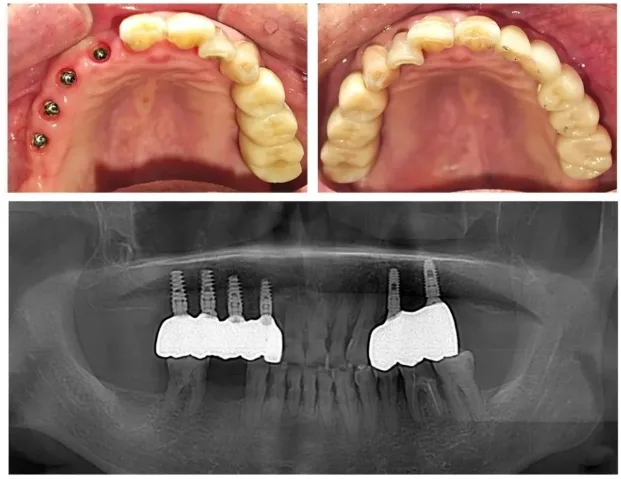

Rozległa implantacja obu łuków i globalna augmentacja – kompleksowy plan z jednego pliku CBCT

Pacjenci wymagający implantacji w wielu miejscach obu łuków jednocześnie – po wielozębowych stratach, zaawansowanej chorobie przyzębia, planowaniu All-on-4/6 dla obu szczęk lub rozległych rekonstrukcjach protetycznych – potrzebują danych o kości w całym układzie. Dwa oddzielne badania sektorowe (osobno szczęka, osobno żuchwa) generują sumę dawek porównywalną lub wyższą od jednego large FOV, nie dostarczając przy tym spójnego widoku relacji między łukami.

CBCT szczęki i żuchwy generuje pełną trójwymiarową mapę obu łuków: lekarz planuje implanty we wszystkich kwadrantach jednocześnie na jednym modelu, widzi dostępną kość w każdym miejscu, identyfikuje regiony wymagające regeneracji kości lub augmentacji i ustala sekwencję etapów przed pierwszą wizytą zabiegową. Planowanie wieloetapowe na jednym pliku eliminuje ryzyko pominięcia interakcji między zabiegami w różnych kwadrantach – np. augmentacja w górnym kwadrancie tylnym może wymagać innego harmonogramu czasowego niż implant w żuchwie, co wpływa na protetyczny plan tymczasowy.

Dla pacjentów po rozległych stratach kostnych, gdzie atrofia wyrostka przebiega asymetrycznie, CBCT pełnego łuku jest szczególnie wartościowe. Różna wysokość wyrostka po prawej i lewej stronie obydwu szczęk jednocześnie wpływa na optymalną pionową pozycję implantów i relację protetyczną – dane dostępne wyłącznie gdy oba łuki są obejrzone jednocześnie. Wynik diagnostyczny przekłada się bezpośrednio na strukturę planu protetycznego, w tym planowanie stałych lub ruchomych uzupełnień pośrednich i dobór relacji zgryzowej przy rozległej rekonstrukcji.

Planowanie All-on-4 lub All-on-6 jednej lub obu szczęk

Rekonstrukcja pełnego łuku wymaga wirtualnego planowania nie tylko pozycji każdego implantu, ale i relacji między górną a dolną kością niosącą protetykę. Jedno badanie dla całego układu eliminuje niespójność między planami dla obu łuków.

All-on-4 – stałe zęby na czterech implantach

Pełny łuk protetyczny oparty na czterech implantach – kąty osi i pozycje wszystkich wszczepów planowane jednocześnie na CBCT pełnego łuku z szablonami chirurgicznymi.

All-on-6 – stałe zęby na sześciu implantach

Pełna rekonstrukcja łuku na sześciu implantach – zwiększona stabilność i możliwość implantacji w odcinkach tylnych; pozycje wszystkich wszczepów planowane jednocześnie na CBCT pełnego łuku.